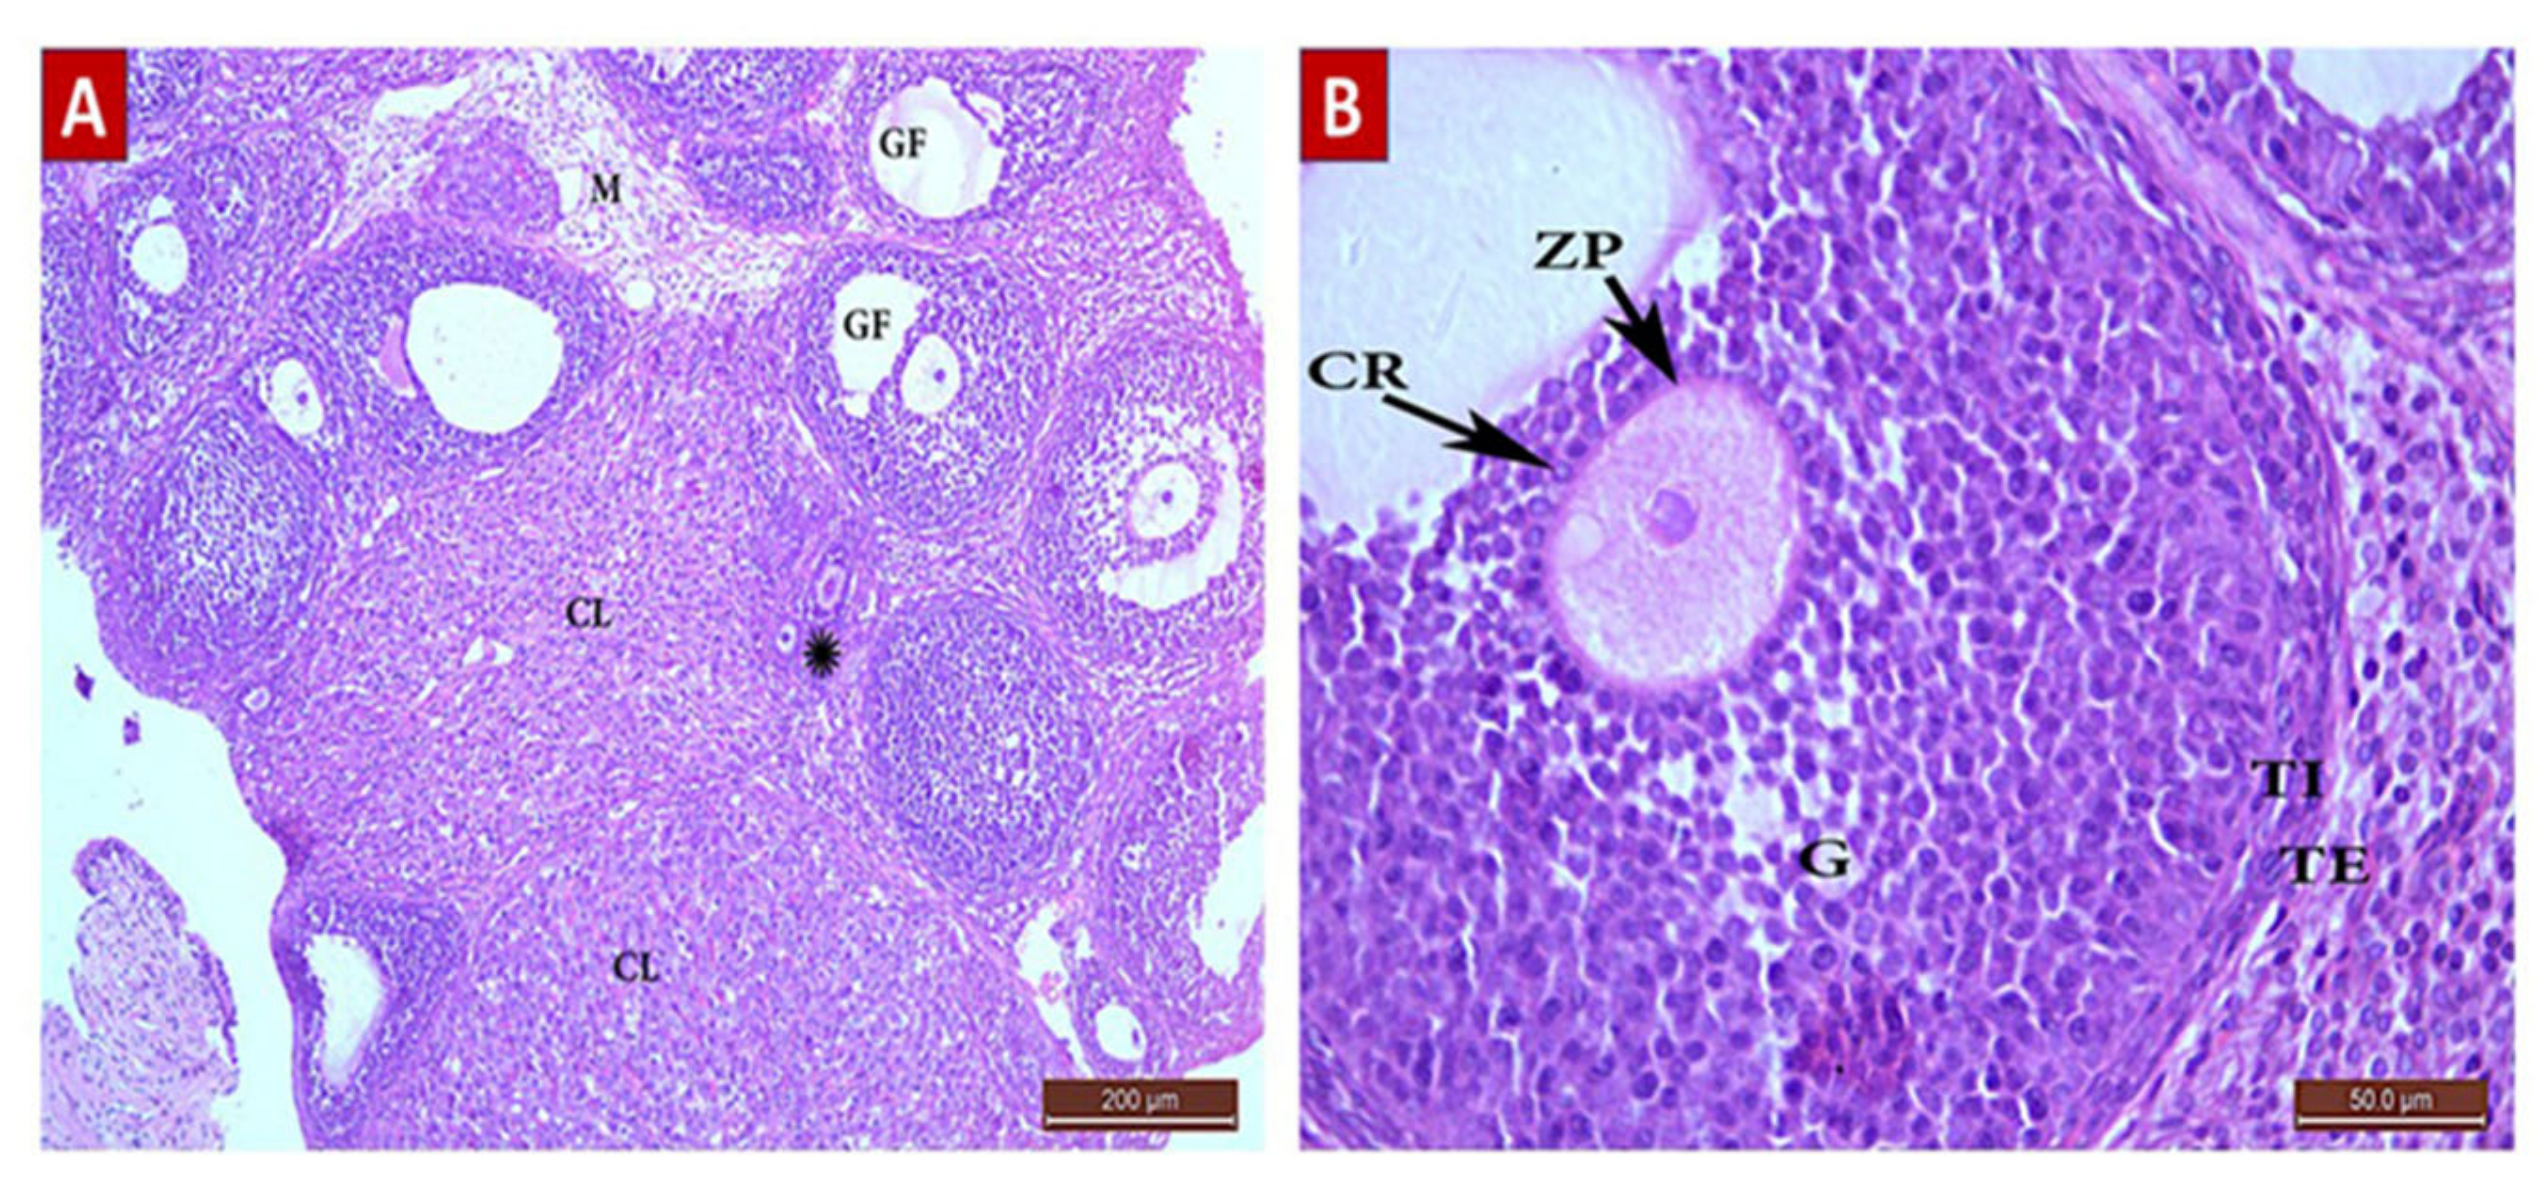

POI Group (Group II, Figure 5)

Diosmin 50 (Group III, Figure 6)